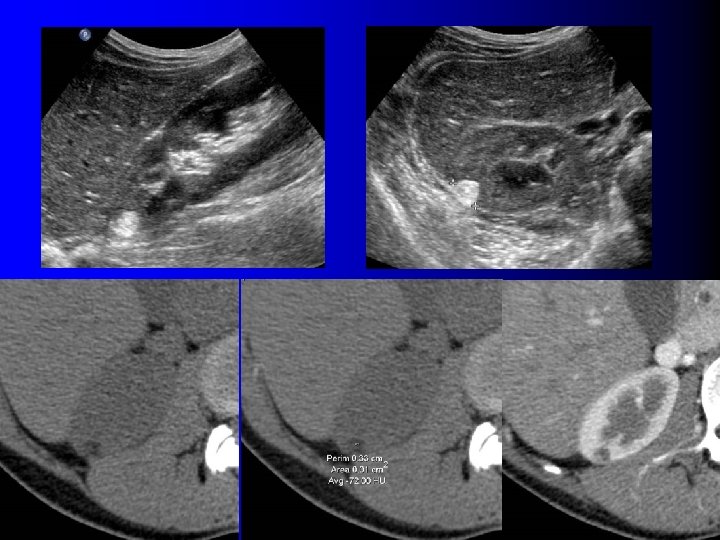

3. Questions pratiques 3. 3. L'absence de graisse élimine-t-elle l'AML ?

3. Questions pratiques 3. 3. L'absence de graisse élimine-t-elle l'AML ?

AML sans graisse l NON l AML: histologie "surprise" dans 2. 5% à 5% des tumorectomies / néphrectomies (1, 2) l Absence de graisse en TDM: – Contingent graisseux très minoritaire (AML "monophasiques") l l Souvent uniquement musculaires, peu vasculaires Graisse < 5% – Contingent graisseux intimement mêlé aux autres : pas de densité graisseuse en TDM (1) Milner J et al, J Urol 2006; 176: 905 (2) Lane B et al, J Urol 2008; 180: 836

AML sans graisse l NON l AML: histologie "surprise" dans 2. 5% à 5% des tumorectomies / néphrectomies (1, 2) l Absence de graisse en TDM: – Contingent graisseux très minoritaire (AML "monophasiques") l l Souvent uniquement musculaires, peu vasculaires Graisse < 5% – Contingent graisseux intimement mêlé aux autres : pas de densité graisseuse en TDM (1) Milner J et al, J Urol 2006; 176: 905 (2) Lane B et al, J Urol 2008; 180: 836

Echographie l Peu l La contributive…. plupart des AML sans graisse sont hypoéchogènes !!!

Echographie l Peu l La contributive…. plupart des AML sans graisse sont hypoéchogènes !!!